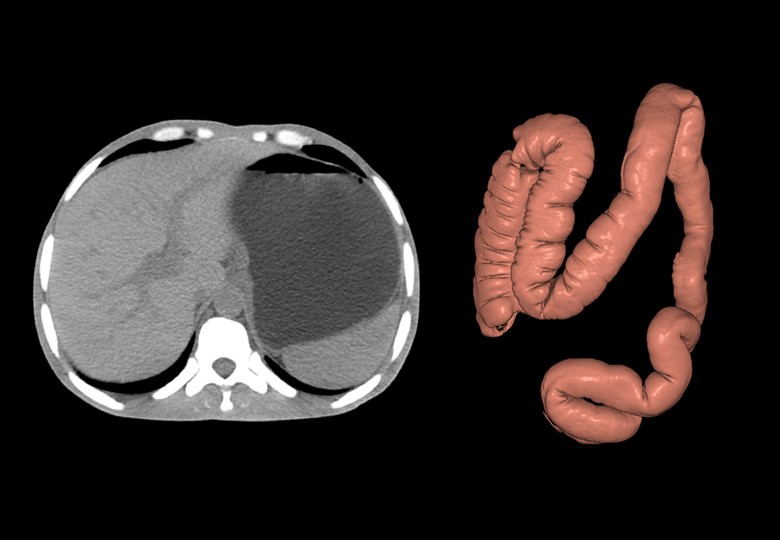

Album d'images cliniques

• Abdomen